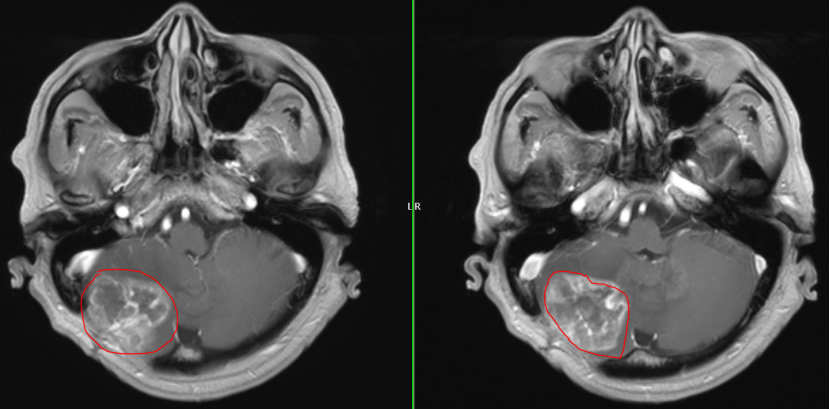

2024年初:肿瘤出现了第一次“跨界”转移。朱先生因剧烈头痛头晕入院,检查发现癌细胞由血液转移右侧小脑半球,约39mm×35mm大小,周焱峰主任带领团队为其行 显微镜下右侧小脑巨大转移瘤切除术,手术顺利完成。术后配合放化疗,病情稳定。

2025年8月:患者头晕、呕吐症状加剧,复查头颅MRI显示右侧小脑半球恶性肿瘤复发,约45mm×35mm大小,周围水肿严重,同时患者合并高血压和糖尿病,治疗难度加大。

术前MRI

术后MRI

历时4小时,神经外科团队仔细分离粘连组织,准确找到肿瘤边界,完整切除了复发的肿瘤,术中监测平稳,最大程度地保护了神经功能。手术顺利完成,所有人都松了一口气.。